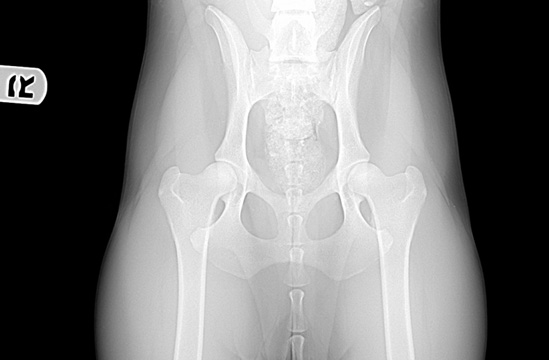

Preliminary hip x-ray submitted to OFA on 10/12/07  results came back GOOD!